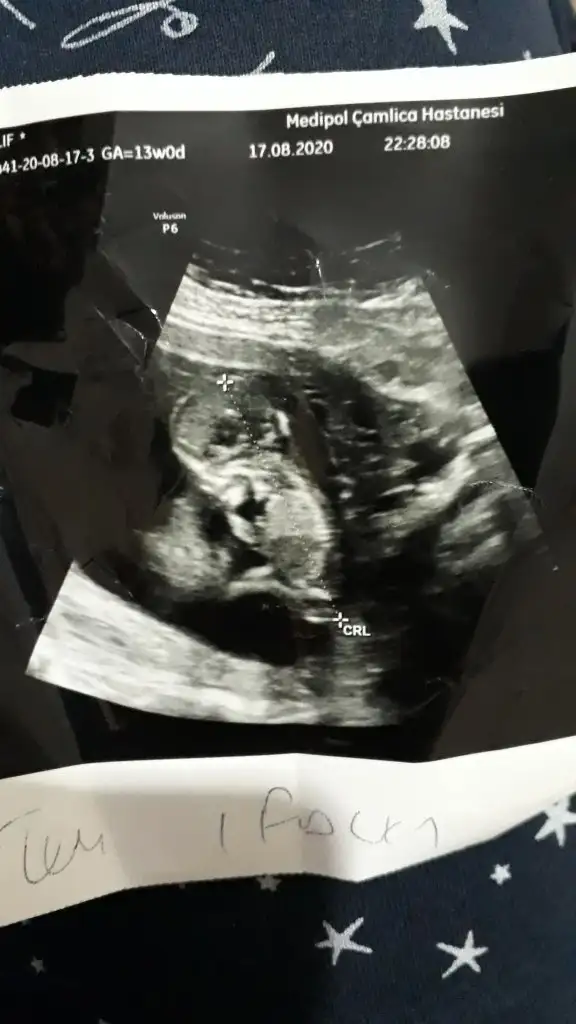

Merhaba 12 haftalik ultrason goruntusuu sizce kizmi erkekmi😍😍